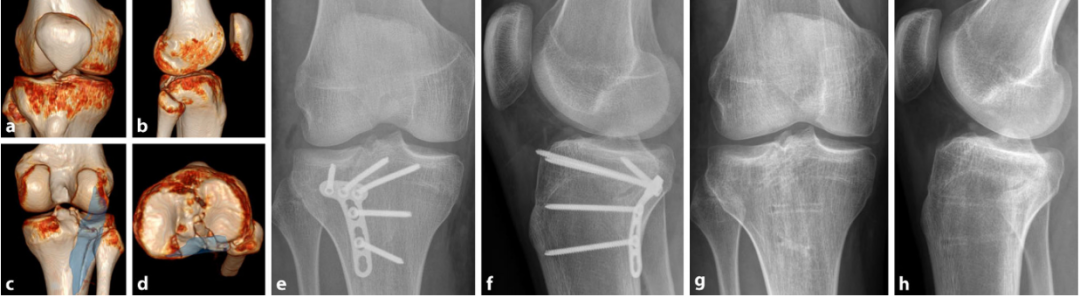

病例3

图17:屈曲型骨折累及后柱

-

俯卧位Lobenhoffer入路(蓝色标记区域)行后柱支撑固定,但关节内视野受限,导致后中央区(Krause分类PZ区)骨折块未实现解剖复位。

经皮固定胫骨平台外侧及内侧骨折延伸部分。

a–d 术前计划CT(计算机断层扫描)。e, f 术后首次体位验证。g, h 术后1年随访影像。

病例4

图18:后外侧柱孤立性骨折

俯卧位Carlson后外侧入路 或 Frosch入路后侧部分 行骨折固定。

a–d 术前计划CT(计算机断层扫描)。e, f 术后首次体位验证。g, h 术后1年随访影像(因前方螺钉尖端突出引起不适,已行内固定取出术)。